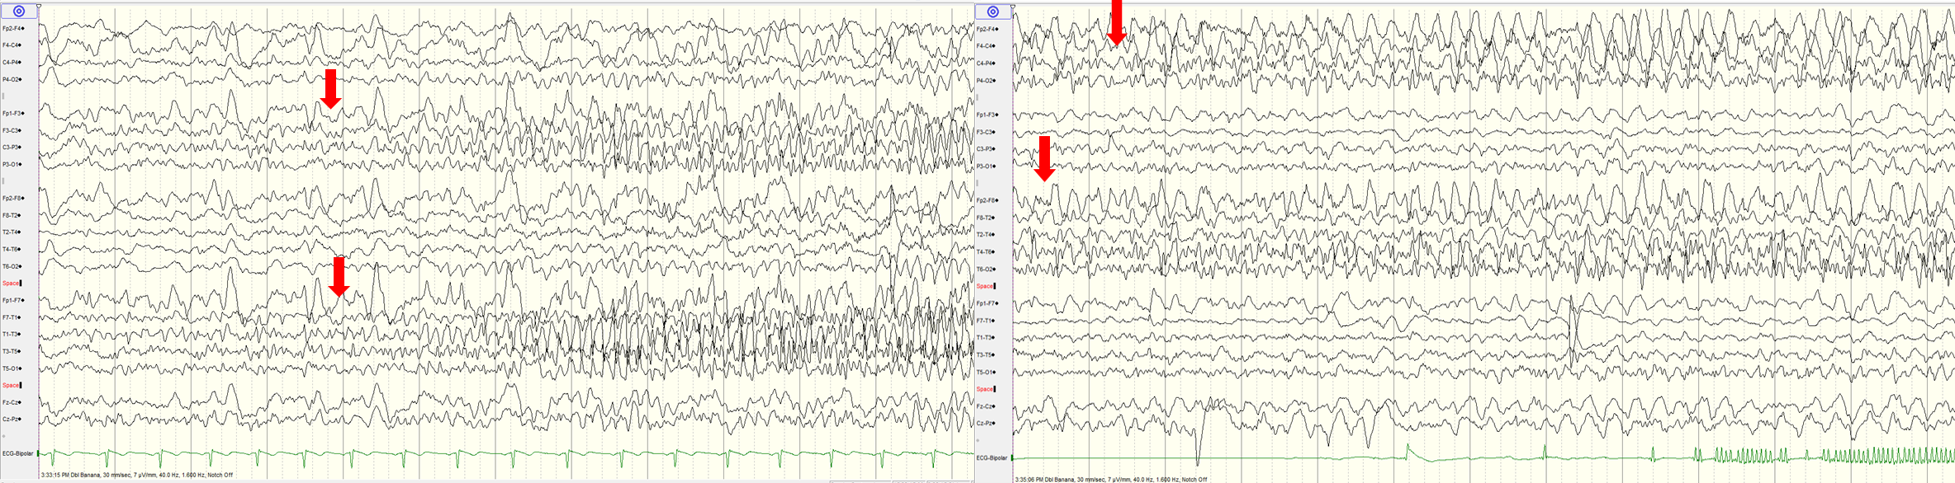

Question: After 3 days of a febrile illness, a previously well 19 years old developed focal seizures with loss of awareness. The seizures progressed to generalised tonic-clonic seizures and convulsive status epilepticus requiring sedation and ventilation in intensive care. cEEG during in ICU shown below. What would be the likely diagnosis?

Explaination: While earlier literature generally used NORSE for adult patients and FIRES for children, working definitions do not make this distinction, and both terms now apply in all ages<br><br>Three common early patterns<br>- initially infrequent seizures gradually evolving into status epilepticus<br>- beta-delta complex resembling delta brushes<br>- characteristic seizure onset pattern with focal fast activity with shifting seizures<br><br>Other patterns reported in Adults periodic discharges (generalised, lateralised, bilateral independent and multifocal) and multiple seizure patterns (generalised, focal and multifocal)